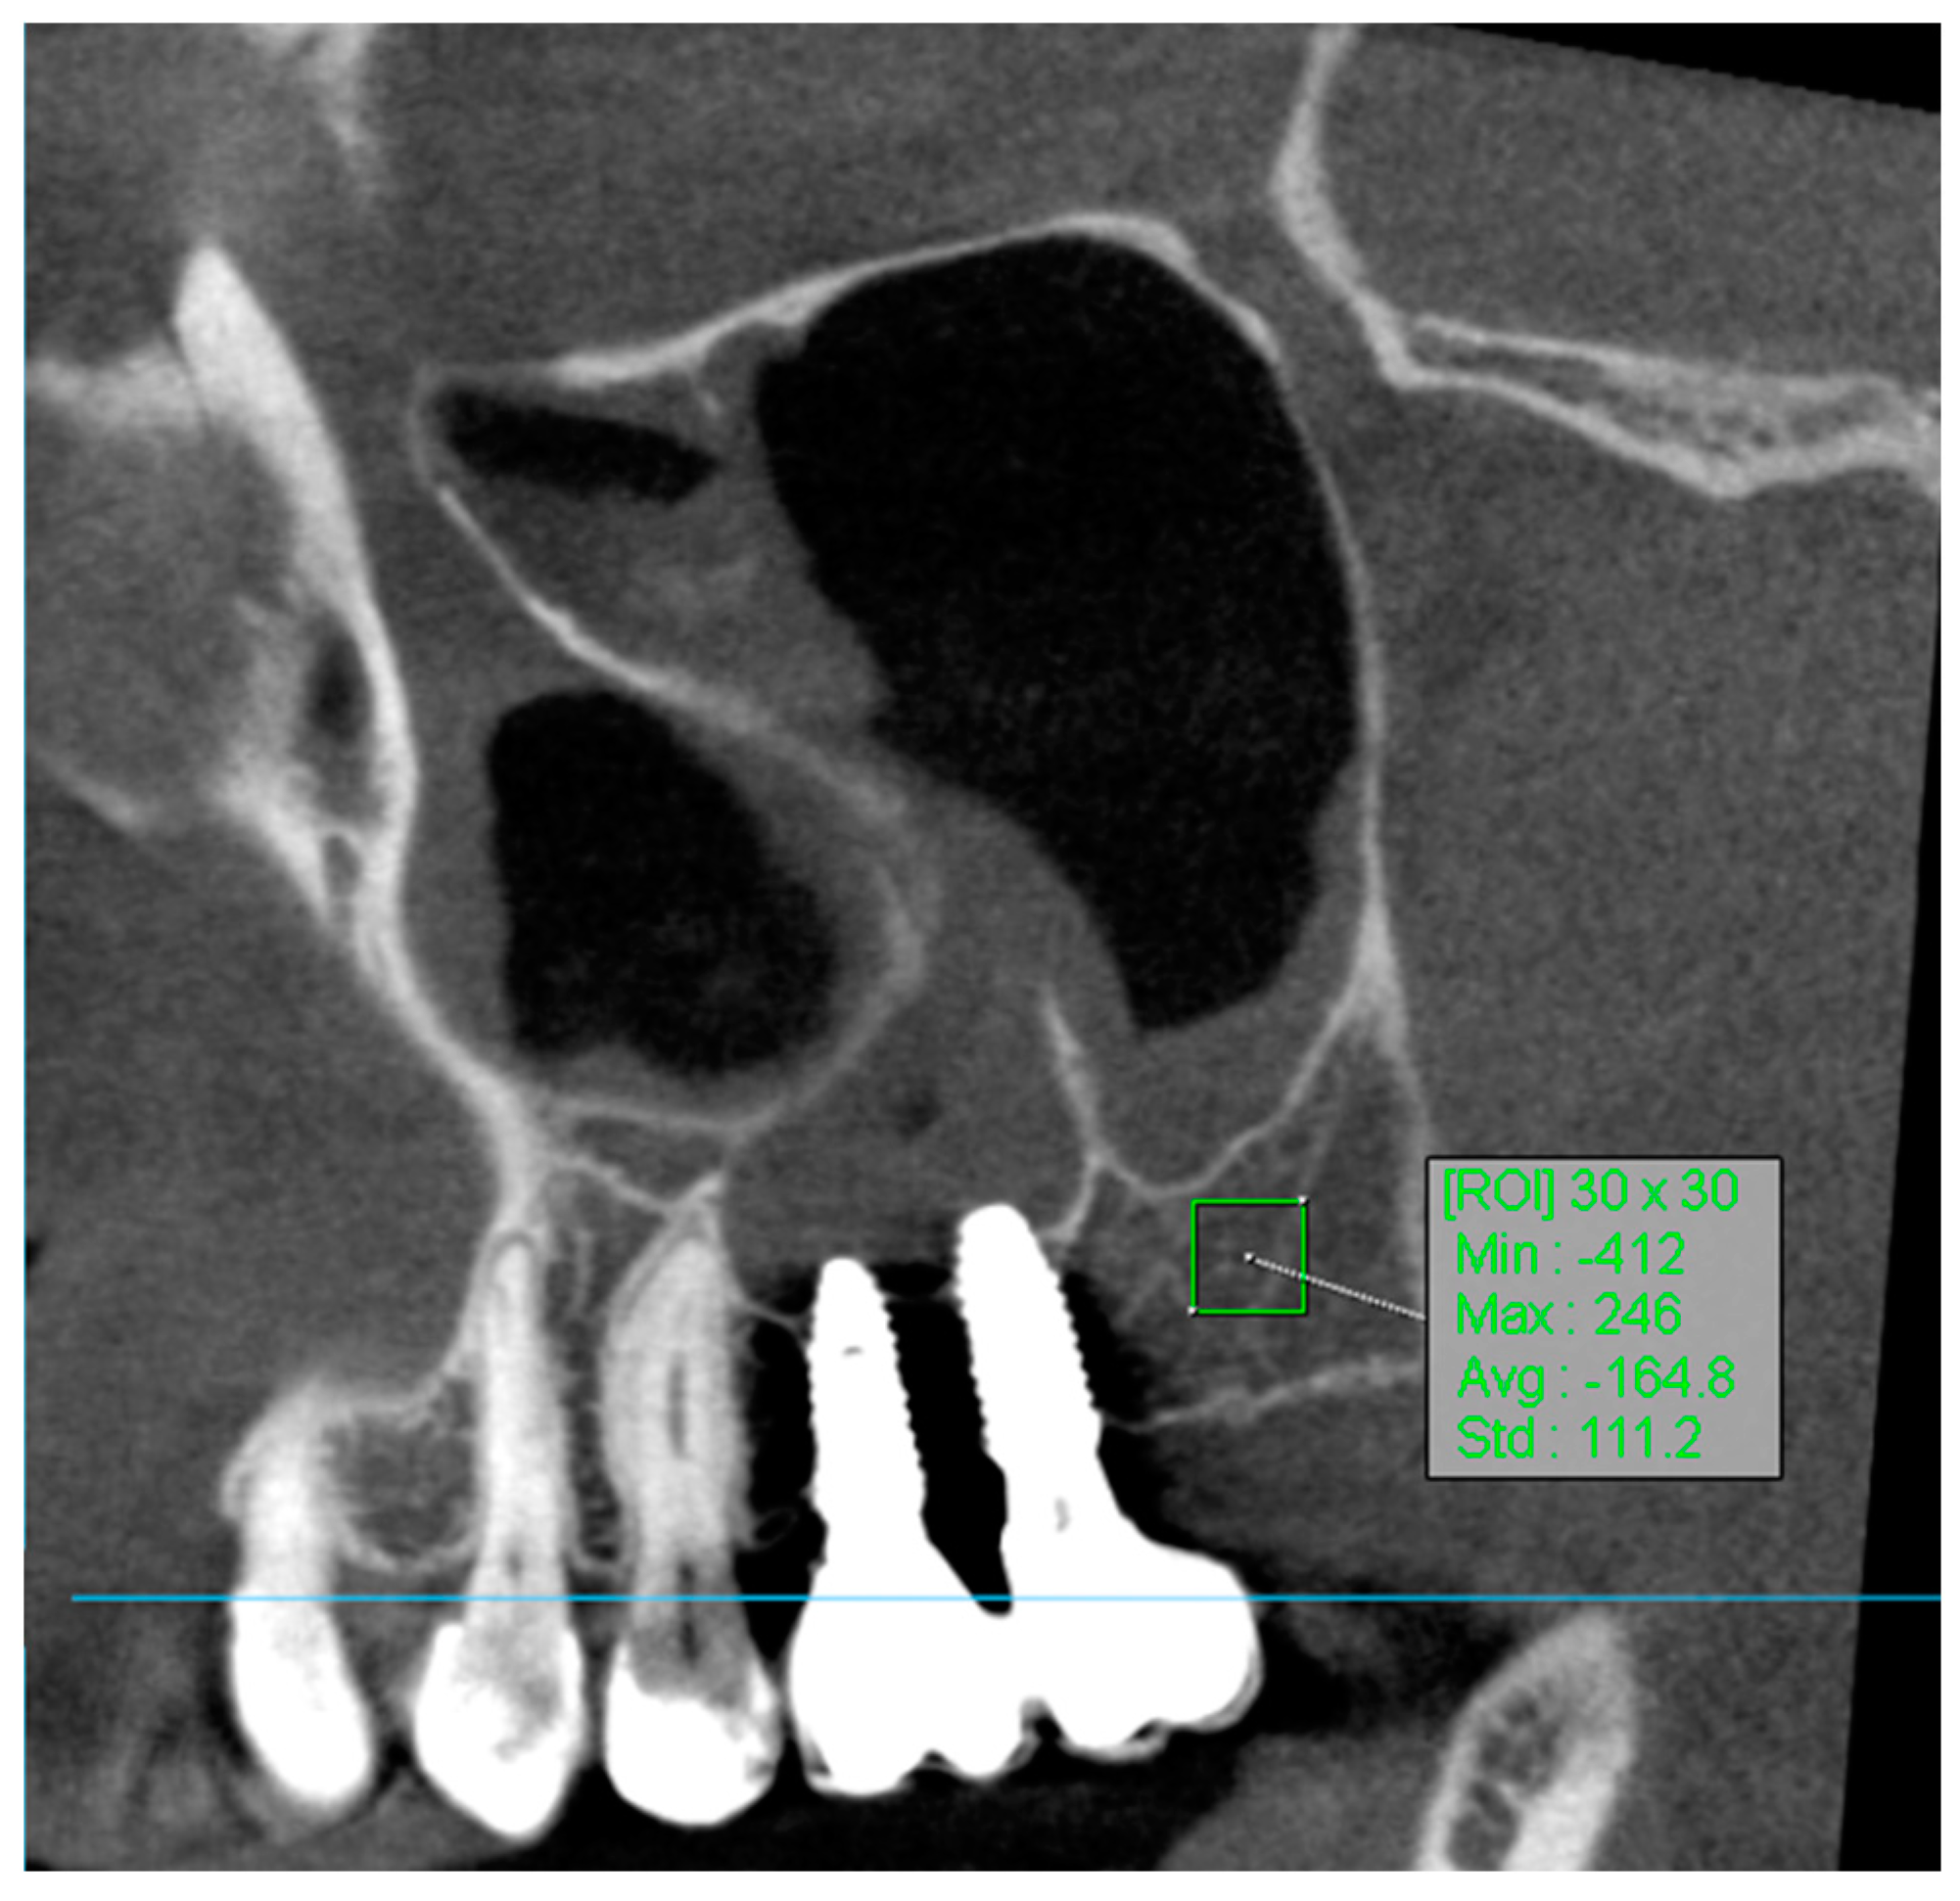

The use of regions of interest (ROI) in CBCT imaging is highly beneficial for accurately correlating gray values with Hounsfield Units (HUs) (Figure 4). This approach enhances diagnostic precision and treatment planning in dental radiology [32].

Figure 4.

ROI measurement.

To determine the region of interest (ROI) in the volumetric analysis of bone tissue using manual segmentation, the methodology involved several key steps. CBCT images were processed using the OnDemand3D App, an application specifically designed for such analyses. The OnDemand3D App, version 1.0.11.1007, is produced by Cybermed. The polygon selection tool in OnDemand3D was utilized to manually outline the region of bone tissue on the selected slices. Specifically, square areas of 30 × 30 pixels were delineated to achieve precise segmentation of the ROI. This tool allowed for the measurement of minimum, maximum, average, and standard deviation density values within the specified region. To draw the region of interest, the tool options provided choices of [Rectangle], [Circle], or [Polyline], with the square (30 × 30 pixels) selection being used in this analysis.

For volume measurement, the ROI measurement tool in OnDemand3D was used to calculate the volume of bone tissue based on the outlined slices. Accurate slices were defined from a specified starting point to the endpoint within the analyzed bone, using appropriate reference points such as characteristic anatomical landmarks [30]. Bone attenuation values obtained from baseline scans were compared with the results of follow-up examinations after 8 weeks (for the Small-Particle Dentin Group) and 12 weeks (for the Bio-Oss Group and Control Group).